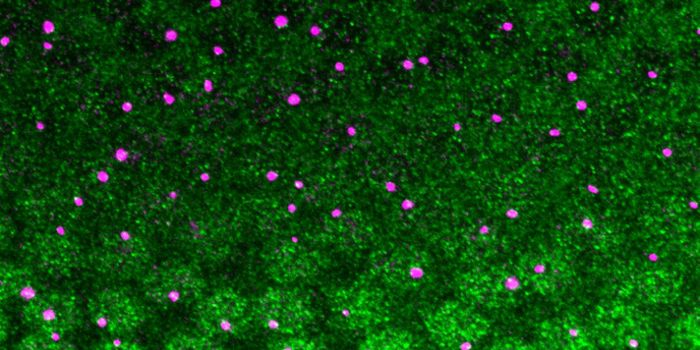

OCT 11, 2021Genetics & GenomicsWhile amyloid plaques are a hallmark of Alzheimer's disease, the neurological disorder has also been linked to inflammat ...